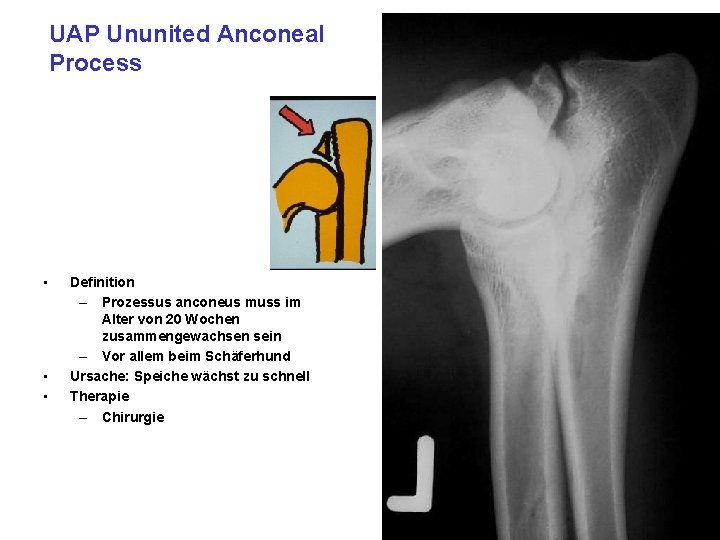

UAP Ununited Anconeal Process • • • Definition – Prozessus anconeus muss im Alter von 20 Wochen zusammengewachsen sein – Vor allem beim Schäferhund Ursache: Speiche wächst zu schnell Therapie – Chirurgie